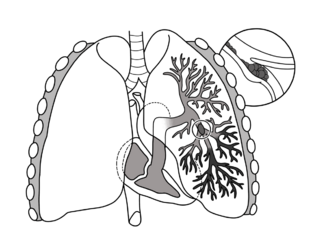

Short description: Blockage of an artery in the lungs

| A lung illustration depicting a pulmonary embolism as a thrombus (blood clot) that has travelled from another region of the body, causes occlusion of the pulmonary bronchial artery, leading to arterial thrombosis of the superior and inferior lobes in the left lung |